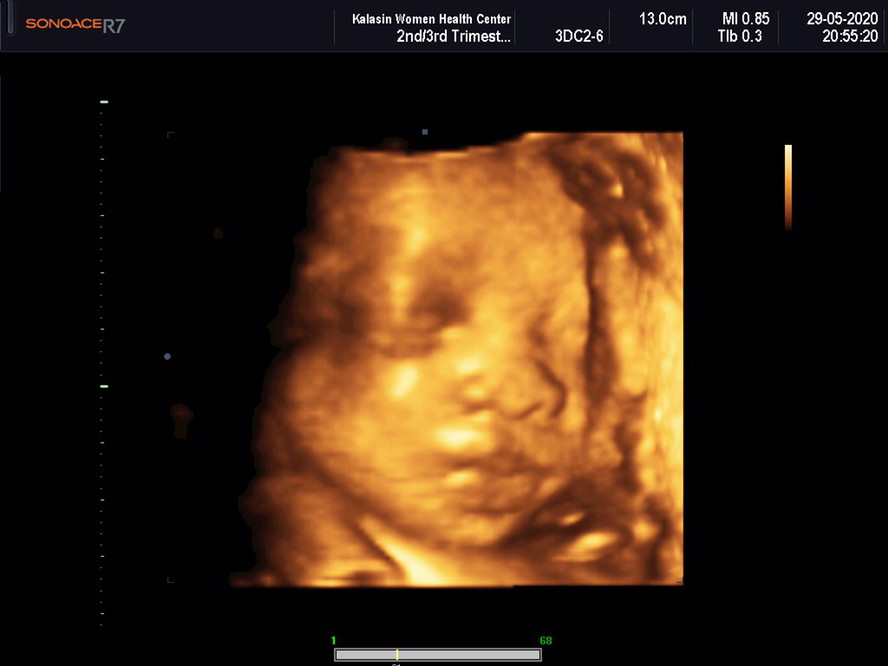

บ้านนี้ 31w ละคะ กำหนดคลอด 6 สิงหา น้อง ผญ #พึ่งไปซาว4มิติมา #เห้นน้องชัดมากอิแม่ปลื้ม ?